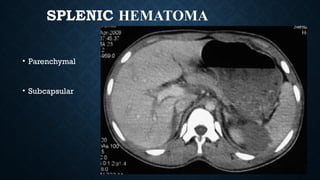

SPLENIC HEMATOMA

• Parenchymal

• Subcapsular

SUBCAPSULAR

HEMATOMA

• Indents splenic

parenchyma